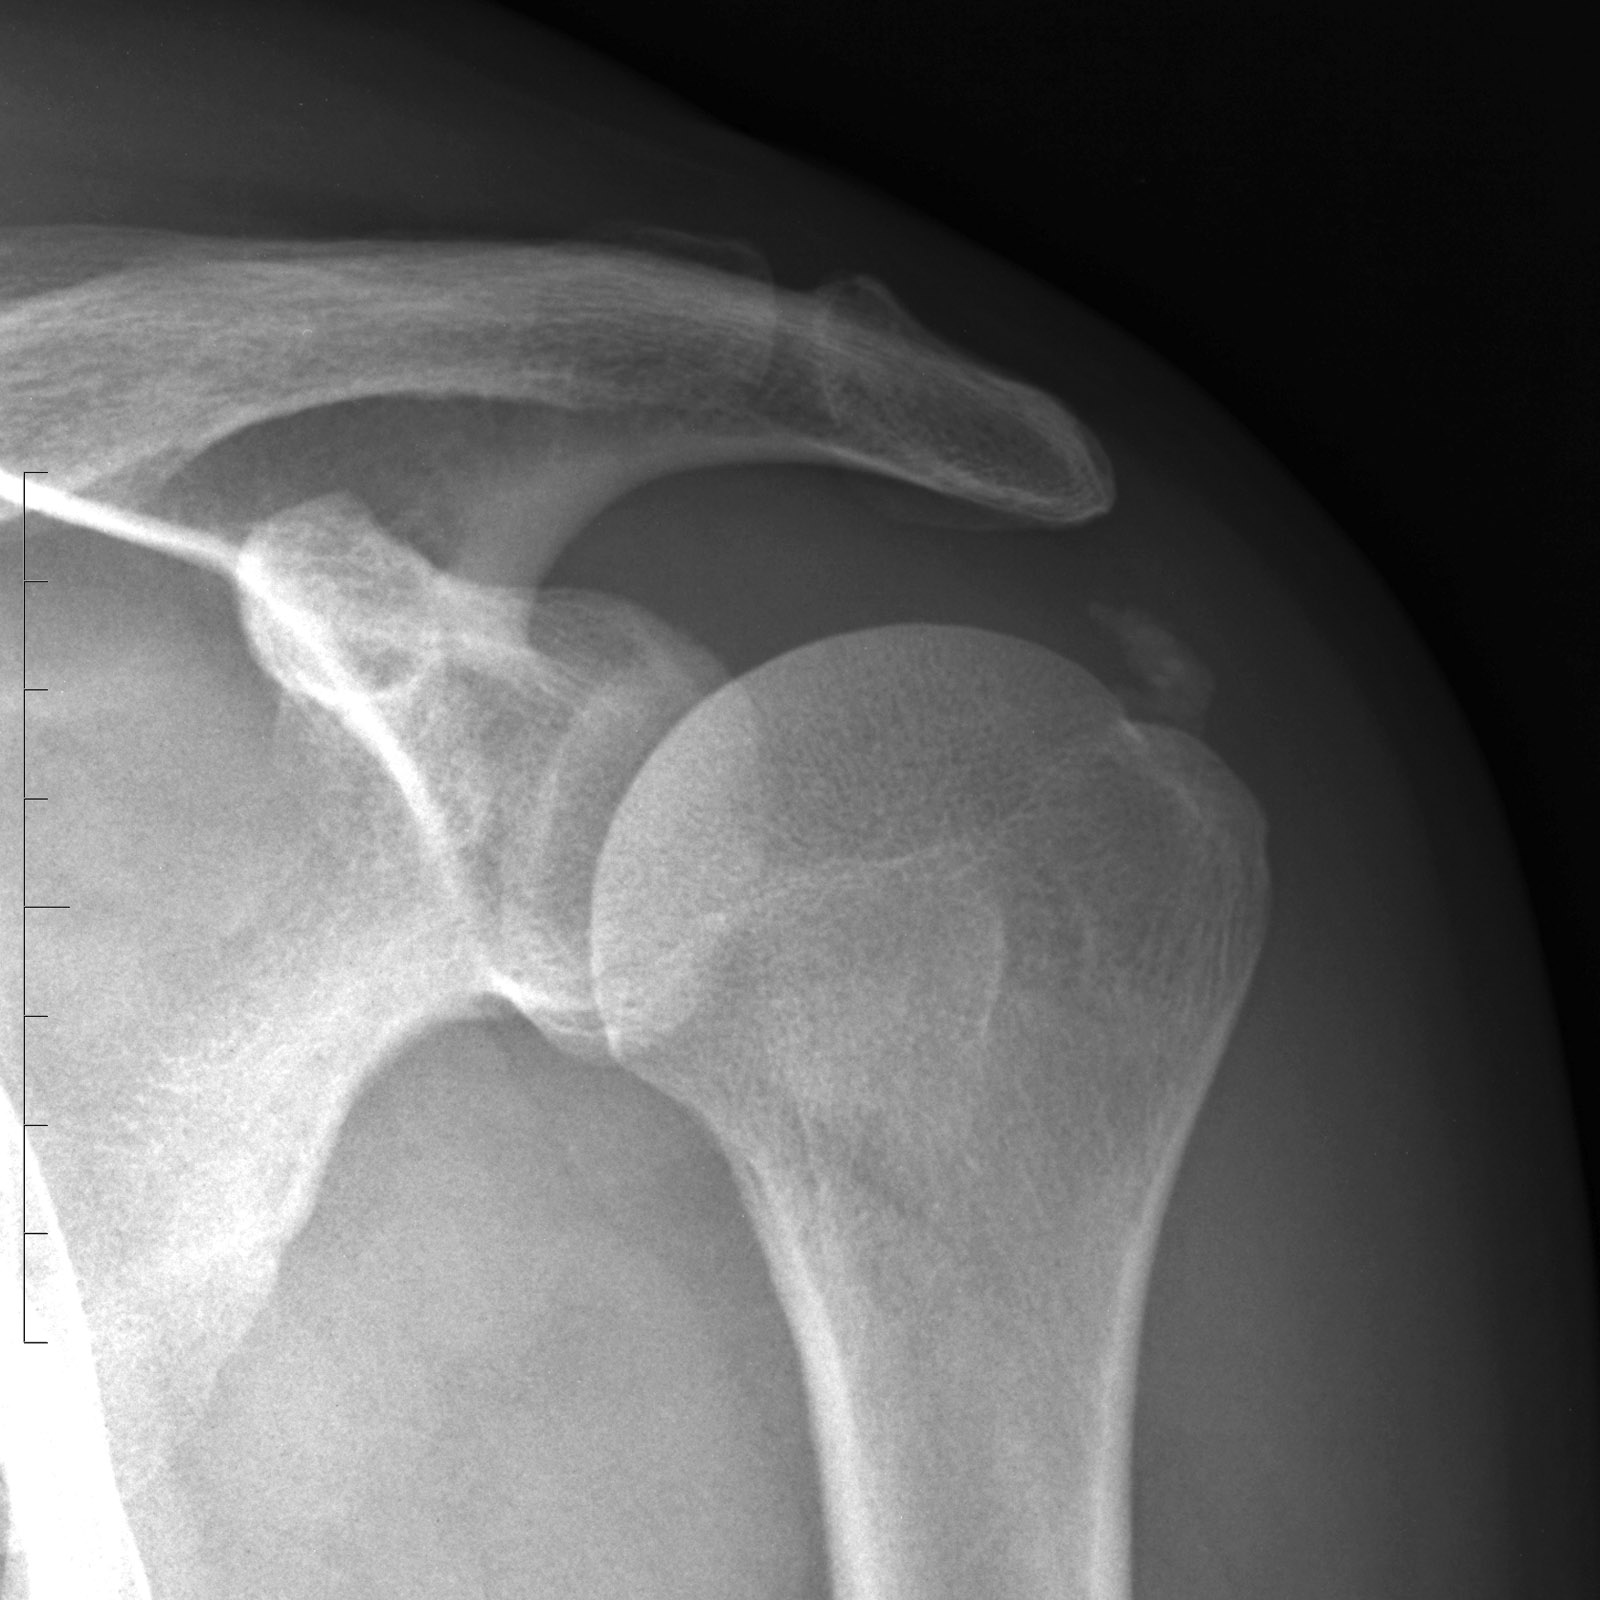

Ο υπερακάνθιος τένοντας αποτελεί μέρος του στροφικού πετάλου και είναι υπεύθυνος για την απαγωγή του βραχίονα. Η ασβεστοποιός τενοντίτιδα είναι πάθηση κατά την οποία έχουμε εναπόθεση αλάτων ασβεστίου στην περιοχή της κατάφυσης του τένοντα στο βραχιόνιο. Η κατάσταση αυτή είναι αποτέλεσμα χρόνιου ερεθισμού του τένοντα του υπερακανθίου λόγω επαναλαμβανόμενων μικροτραυματισμών και εκφύλισής του.

Η λήψη ιστορικού και η κλινική εξέταση επαρκούν για να τεθεί η διάγνωση. Παρακλινικές εξετάσεις όπως ακτινογραφίες, υπέρηχοι και μαγνητική τομογραφία χρησιμοποιούνται για την επιβεβαίωση αυτής.